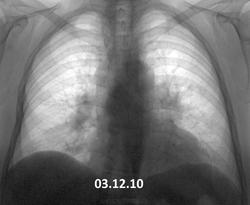

Вот такая динамика. В 2010 г. - в один день вдох-выдох- такая методика у предыдущего флюородоктора. Жалоб нет (кроме сердечных). Согласно КТ ОГК от декабря 2013 - лимфоаденопатия (как говорится - ни вашим, ни нашим). Вроде уже обращено внимание, пациент(ка) это ощутил. Успокоиться?

Картина одинаковая. Увеличение л/узлов средостения и лёгких. Хоть с каким диагнозом наблюдается. Сердечные проблемы здесь ни при чём, они только в ЗАГСе.

Динамики вроде нет.Похоже на саркоидоз.

Есть конечно, тот лимфоузел побольше стал. Диагноз однозначно нужно верифицировать.